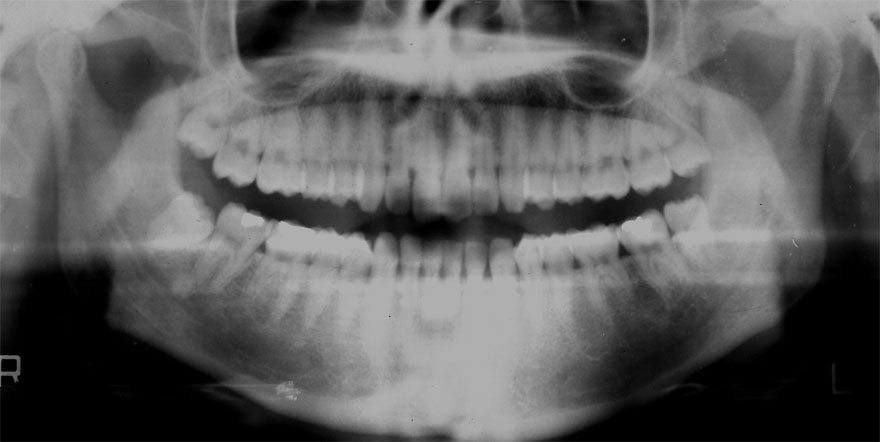

初診時 25歳 男性 平均歯槽骨喪失量:1.43mm

30年後 55歳

平均歯槽骨喪失量:1.56mm

22年間喪失量:-0.14mm

年間喪失速度:-0.005mm

(ケア頻度:4.21ヵ月ごと)